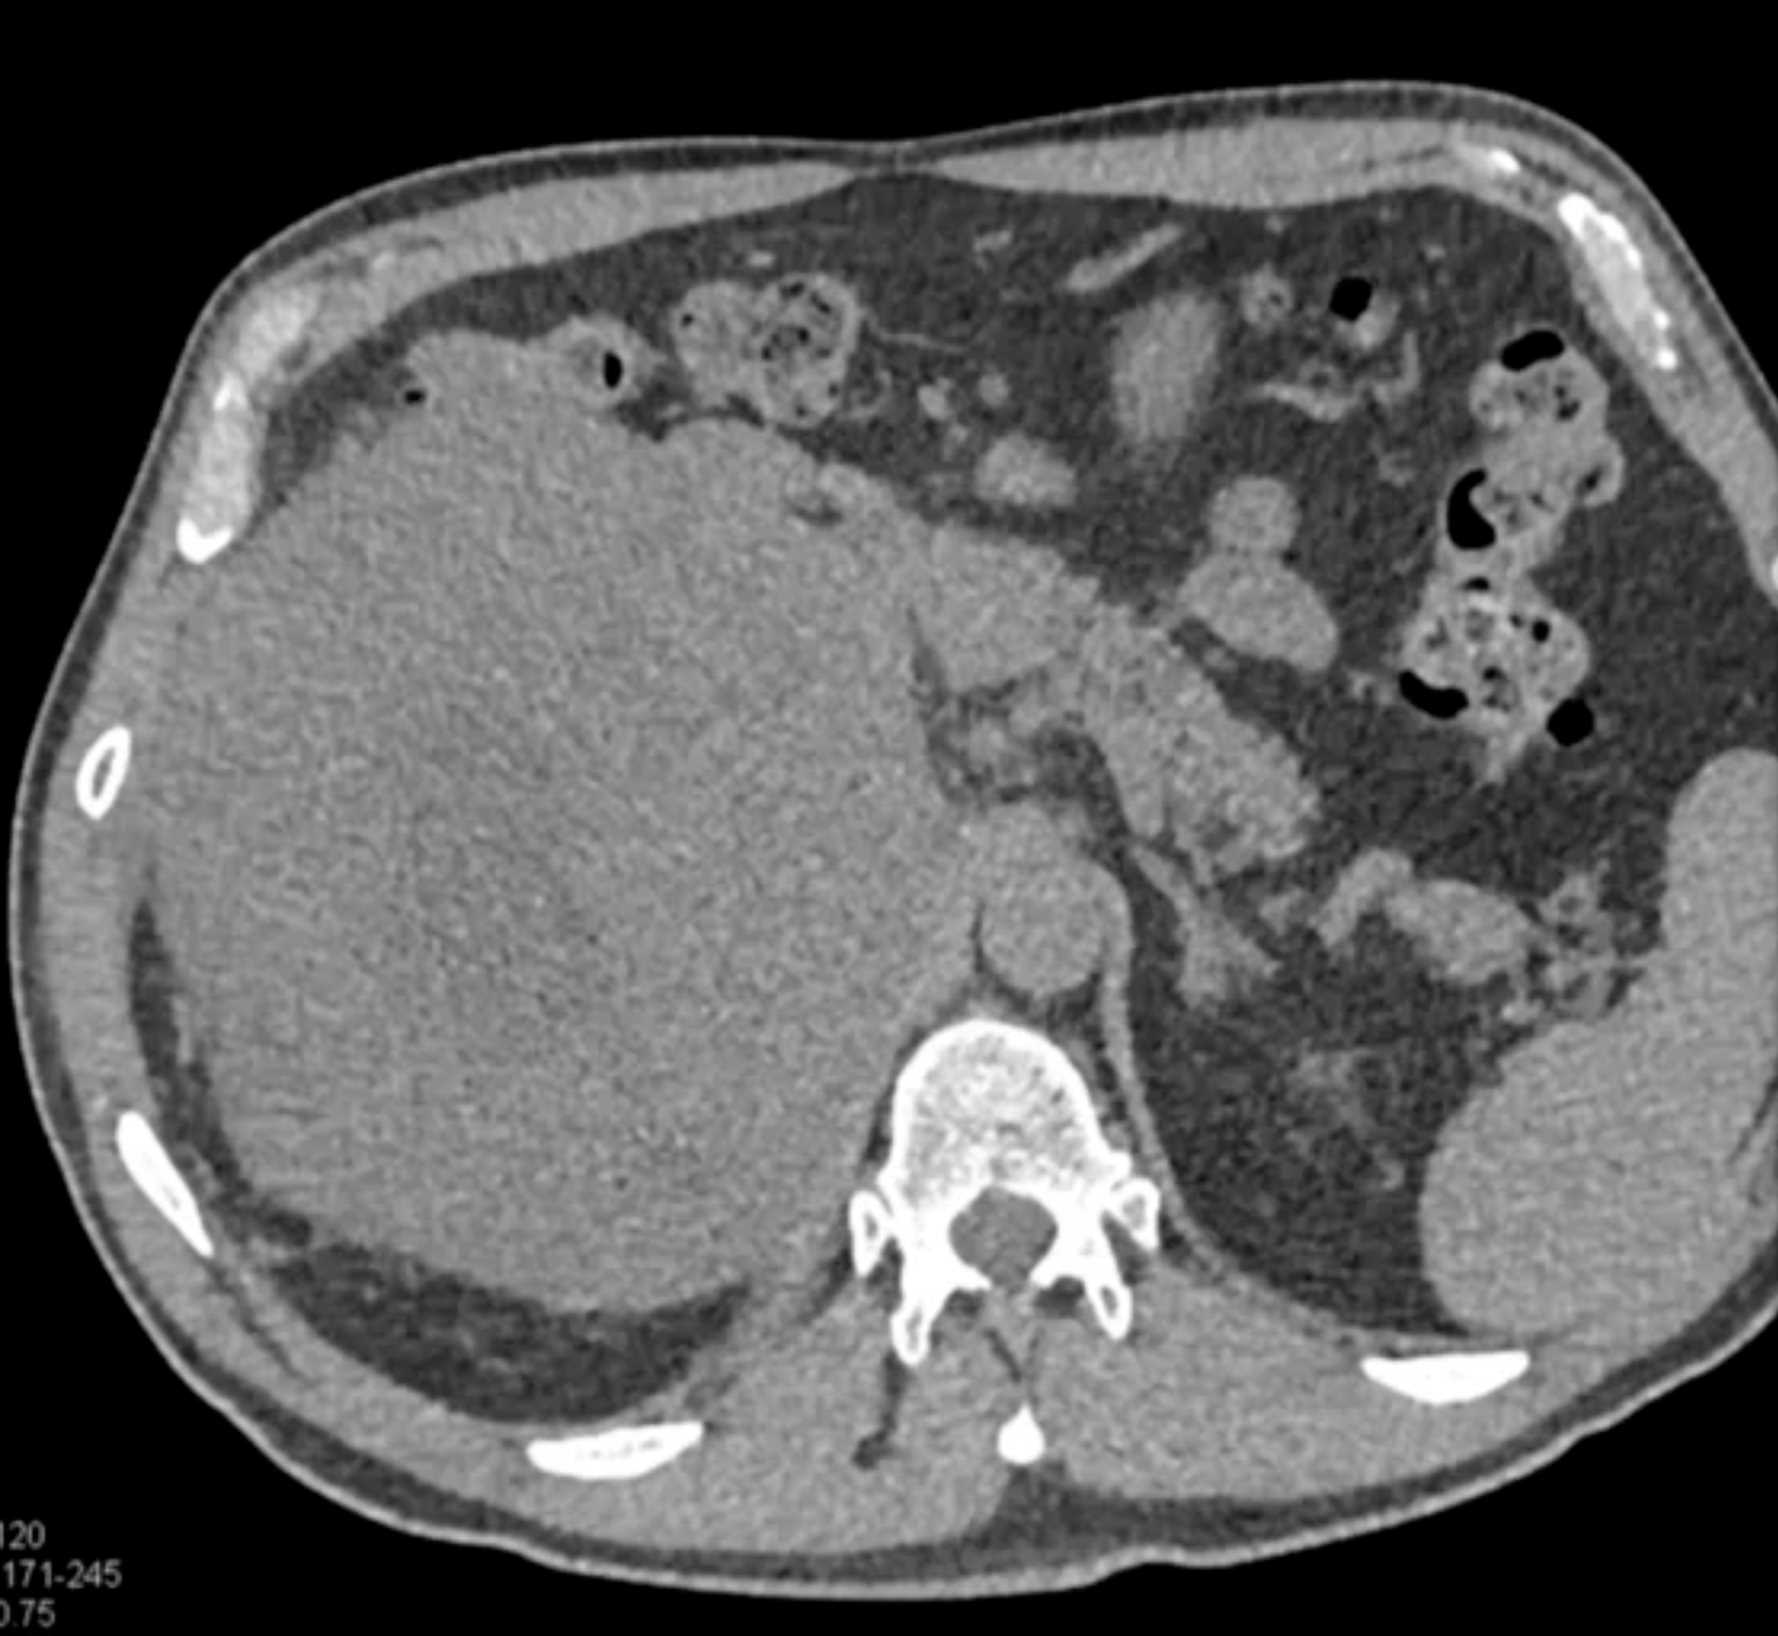

Pleomorphic Sarcoma of the Adrenal